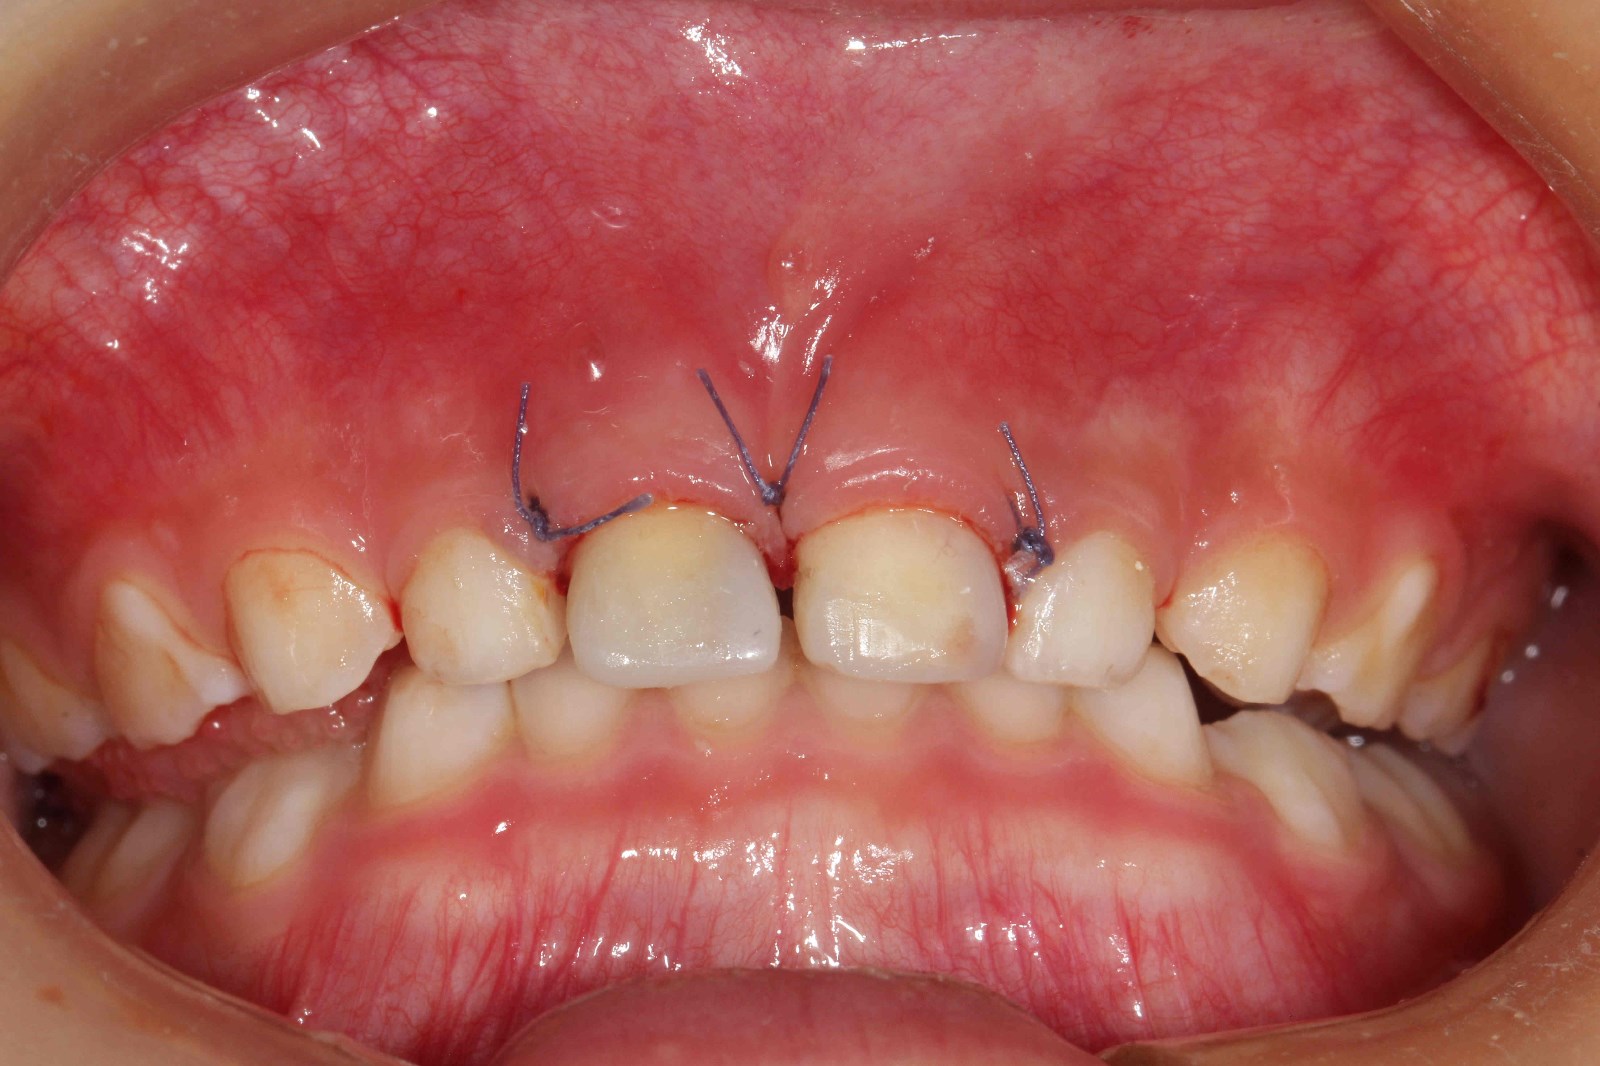

在麻醉医师精准的麻醉配合下,两颗乳牙的治疗及两颗多生牙的拔除快速高效的完成。这一切均发生在患儿“熟睡”的情况下。术毕,停药,患儿复苏,观察,回家。两颗发炎的乳牙已完成治疗并焕然一新,两颗“恼人”的多生牙已告别小主人。